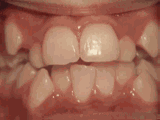

症状表现:牙齿缺失、牙周疾病等导致相邻牙齿无秩序前突。

症状表现:超出正常牙齿颗数,造成牙齿排列不齐,一般需要拔牙。

症状表现:牙齿过多,牙槽骨过窄,使牙齿没有足够空间生长就会造成牙齿排列不齐,需根据情况判断是否拔牙。

症状表现:通俗来讲就是咬牙时无法紧闭,上下牙齿中间有缝。

症状表现:上牙边沿覆盖下牙超过1/3,俗话说的天包地。

症状表现:疾病外因等造成的牙列稀疏,牙槽骨过长或牙齿缺失,导致排列太宽松,零零散散。

症状表现:下牙边沿覆盖上牙超过1/3,俗话说的地包天。